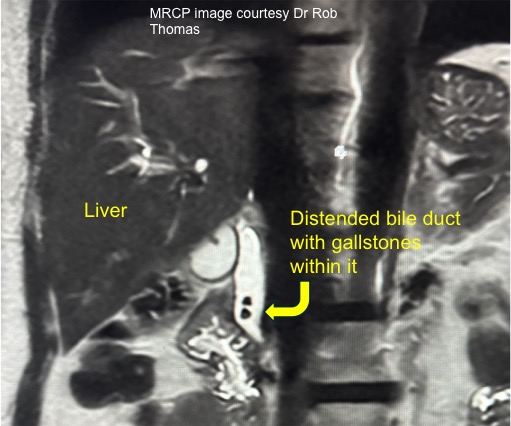

Occasionally, other tests may be required, such as an MRI scan (referred to as MR cholangio-pancreatography or MRCP), CT scan, or radio-isotope tests such as HIDA scans. An MRCP will show the anatomy of the liver and the gall bladder, the bile duct, as well the surrounding organs such as the pancreas (see illustration).

What if I have a stone in my bile duct?The adjacent picture is of an MRI scan that shows stones in the gall bladder and in the bile duct. If stones in the bile duct are identified beforehand, then they can be removed through an endoscope (at an ERCP) before the operation to remove the gall bladder.